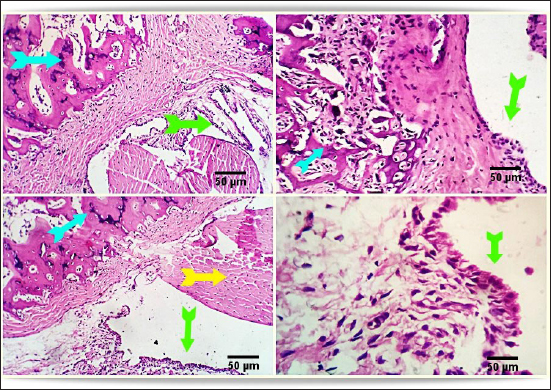

FCA/NHVH unexpectedly revealed a moderately effective treatment efficiency. The cartilaginous cap in this instance demonstrated a regeneration process with slow ossification and remodeling, but there was also a noticeable osteoclastic reactivity, most likely to phagocytize the leftover osteonecrotic debris. In tandem with these sessions of treatment, the inflammatory responses subsided gradually, and the lesions in the synovial and soft tissues healed completely, leaving the synovial membrane looking normal (Fig. 5).

Fig. 5. Photomicrograph from rat’s hip joint of FCA/NHVH showing regenerative process with gradual ossification and remodeling process in the cartilaginous cap (light blue arrow). phagocytosis of the remaining osteonecrotic debris (yellow aarrow), synovial -soft tissue lesions are resolved with consequent complete healing and normally looking synovial membranous lining (green arrows). Scale bars 50 um.